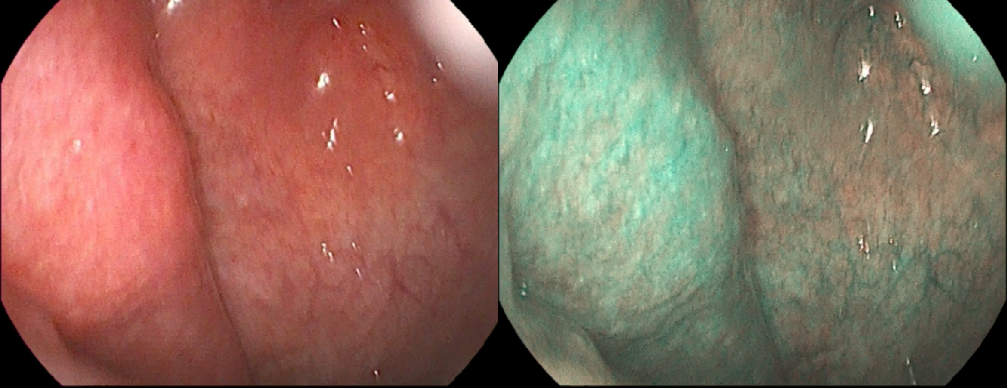

在鼻咽镜检查中,发现镜下鼻咽部粘膜光滑,未见肿瘤性病变(图2),考虑病变位于黏膜下,穿刺活检难以取到,故未取组织,镜下的直观表现不支持鼻咽癌诊断。此期间,患者听力、视力逐渐下降,直至双眼完全失明,听力也很微弱。我们感同身受,十分揪心,患者和家属更是着急万分,多次要求不等病理结果就尽快放疗!但我们深知没有正确的诊断就没有有效的治疗,目前鼻炎癌诊断疑点重重,因此一边对症治疗、一边安抚病人情绪并解释正确诊断的重要性,同时立即召集我院头颈肿瘤MDT成员进行会诊。会诊中,以耳鼻喉一科单春光教授、口腔外科杨威教授、医学影像科高国栋副教授、病理科吴文新教授及放疗科薛晓英教授为首的头颈肿瘤专家团队详细分析梳理了患者的疾病演变过程、临床症状与体征、影像学、鼻咽镜下表现等等,一致认为鼻咽癌诊断疑点重重,需要再次活检明确诊断。建议:1、由耳鼻喉科尽快行鼻内镜下切开活检;2、召集更大范围的MDT联合会诊,讨论是否有其他良性疾病的可能及可能的治疗方案。